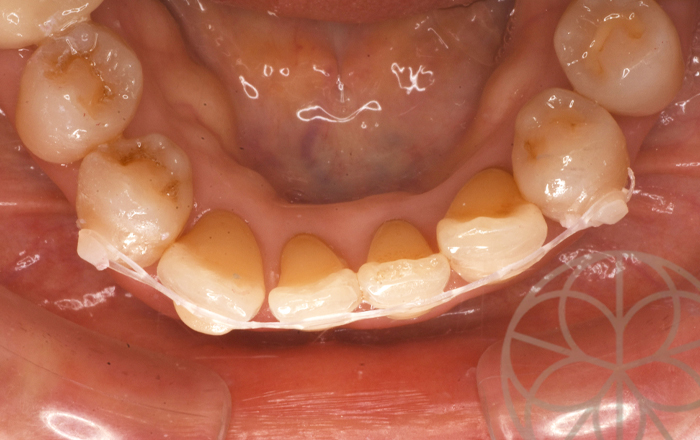

治療前状況①

50代女性、左下の差し歯が抜けたところの改善を主訴に来院されました。

しかし患者様の話を伺っていると、前歯の見た目の部分も気になるとのことで、この色の問題や、歯並びが反対になっていることはなかば諦めているとのことでした。

治療前状況②

レントゲン写真では、多くのカリエスがあり、処置が必要であること、また左下6番の歯は、破折しており、インプラント治療が必要な状態であることを説明をさせていただきました。